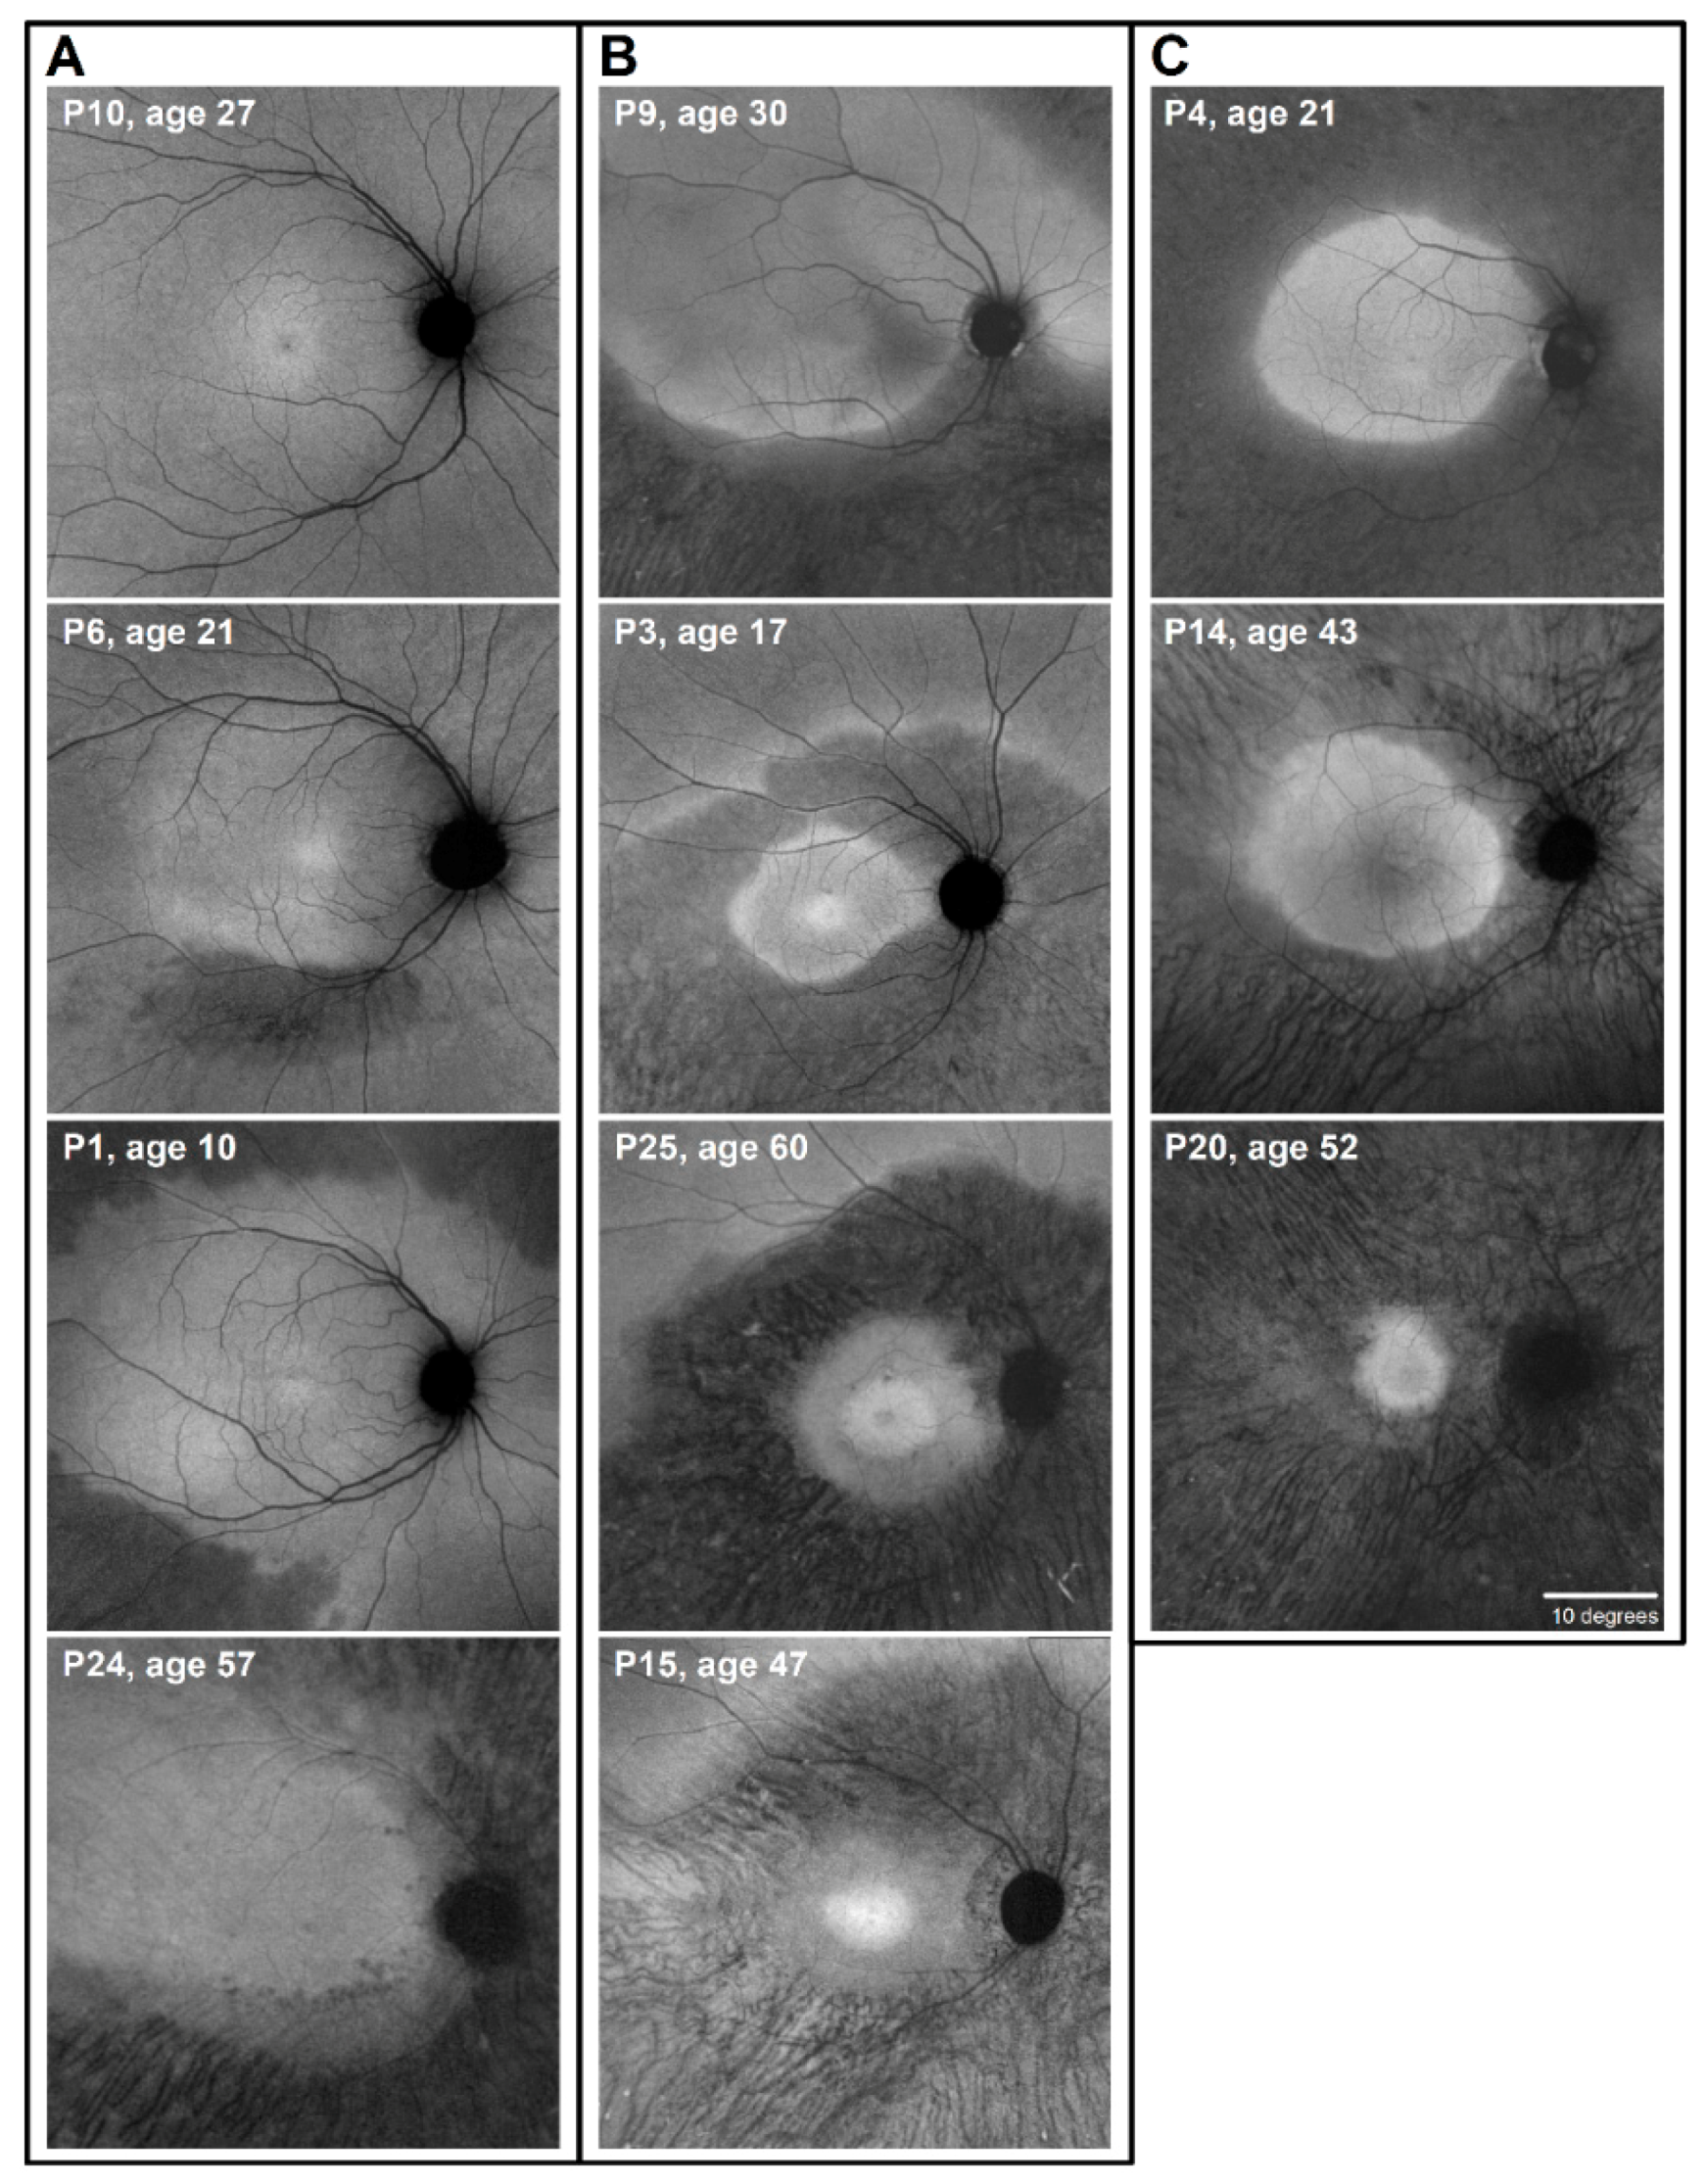

2.1. Autofluorescence (AF) Imaging as an Outcome Measure in RHO-adRP

4.2. Near-Infrared Autofluorescence Imaging